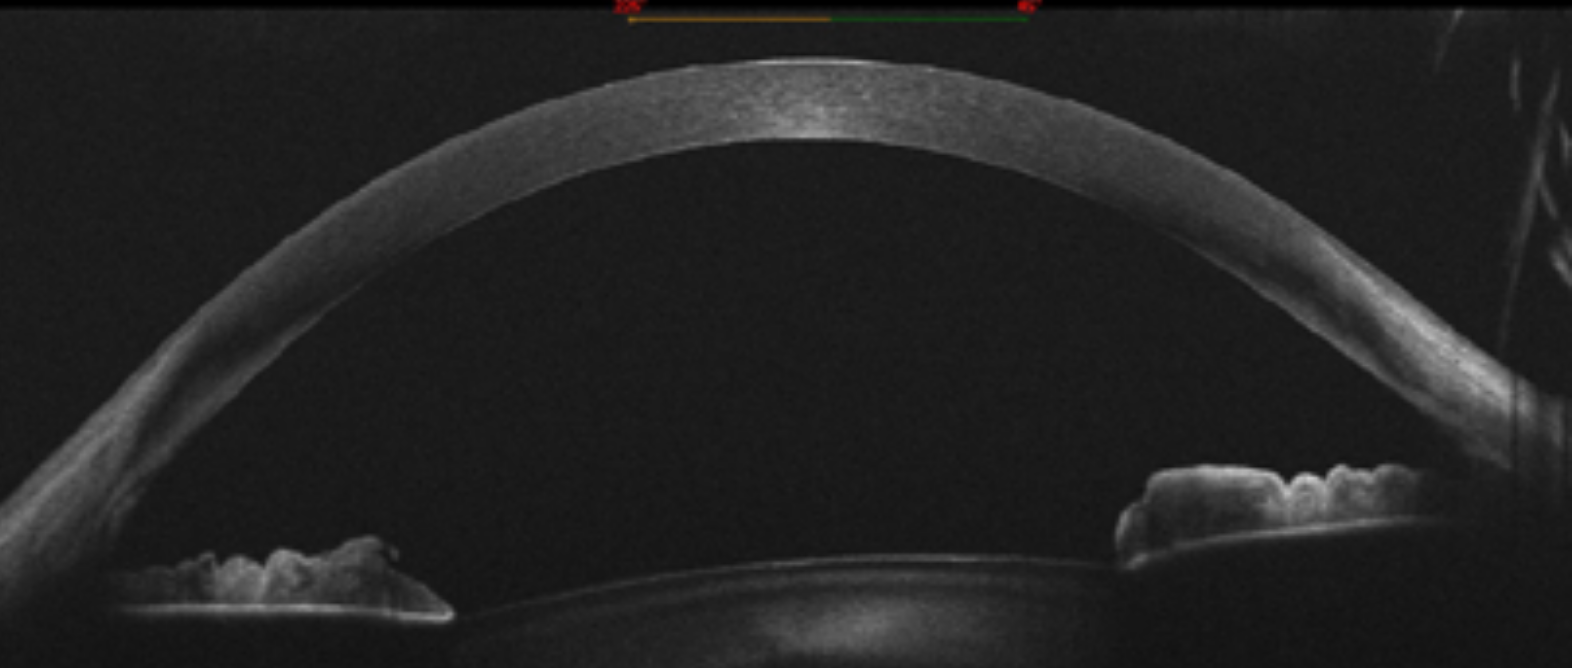

Efficacy of Intrastromal Corneal Ring Segments Combined With Flash Collagen Cross-Linking in Keratoconus

Surgical Options for the Refractive Correction of Keratoconus: Myth or Reality

Taller de Anillos Intracorneales

Conquistando el Queratocono

Curso de Queratocono